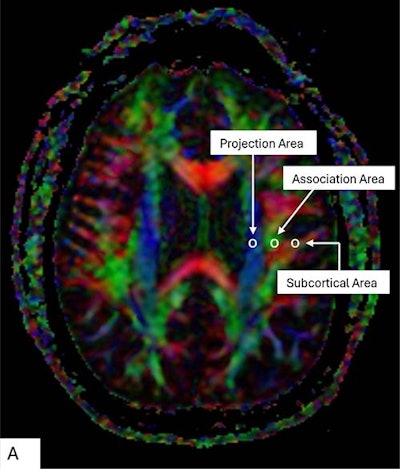

Color display of diffusion tensor imaging indicating the distribution of projection fibers (z-axis: blue), association fibers (y-axis: green), and the subcortical fibers (x-axis: red). Three regions of interest are placed in the area with projection fibers (projection area), association fibers (association area), and subcortical fibers (subcortical area) to measure diffusivities of the three directions (x, y, z).Color display of diffusion tensor imaging indicating the distribution of projection fibers (z-axis: blue), association fibers (y-axis: green), and the subcortical fibers (x-axis: red). Three regions of interest are placed in the area with projection fibers (projection area), association fibers (association area), and subcortical fibers (subcortical area) to measure diffusivities of the three directions (x, y, z).RSNA